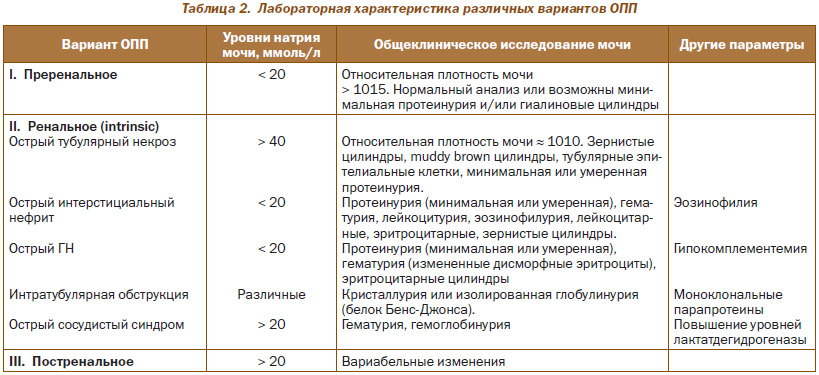

Диагностика острого повреждения почек

Диагностика различных причин почечной (intrinsic) ОПП требует проведения тщательного анализа клинико-лабораторных и инструментальных исследований. Лабораторному исследованию мочи отводят важное место в дифференциальной диагностике (табл. 2). Нередко при данном варианте ОПП для уточнения его особенностей необходимо проведение прижизненного морфологического исследования.